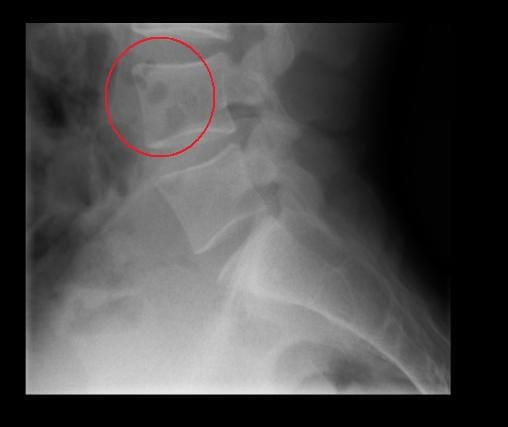

Radiografía normal ? Manchas negras que son ?

Resulta que estoy un poco inquieto y preocupado debido a que me mandaron a sacar unos rayos X lumbares pero revisándolos observe esas manchas negras en una vertebra, al parecer y por lo que he visto en varios lados es aire o burbujas de gas, quisiera que me sacaran de dudas porque estoy muy preocupado, ¿algún experto en interpretación de radios equis podría orientarme?